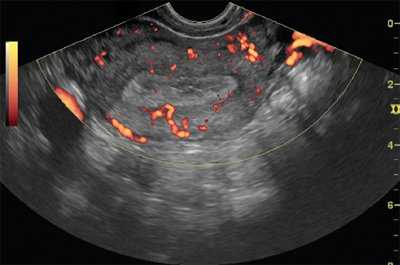

По данным ультразвукового исследования (УЗИ) органов малого таза матка anteversio, -flexio, с четкими, ровными контурами, размерами 52,2 × 45 × 57,4 мм. Стенки не утолщены, структура миометрия однородная. Полость матки не деформирована. М-эхо - 14,5 мм, соответствует 2-й фазе менструального цикла. В проекции левых придатков определяется округлое гипоэхогенное образование размерами 52 × 50 × 50 мм с четкими контурами, с кровотоком по периферии и в центральных зонах, индекс резистентности IR = 0,58, максимальная скорость кровотока (Vmax) - 10 см/с. К образованию прилежит овоидное образование 21 × 15 × 17 мм, объем - V = 2,85 мл. Правый яичник визуализируется, размерами 34 × 29,5 × 31 мм, V = 16 мл, определяются единичные фолликулы до 5 мм. Свободной жидкости в малом тазу до 30-50 мл (рис. 1).

С целью исключения ЗНО яичника пациентке выполнено дообследование с применением УЗИ с внутривенным конт-растным усилением (КУУЗИ). После пункции кубитальной вены введен катетер, через который вводился контрастный препарат Соновью, разведенный в 10 мл физиологического раствора натрия хлорида (0,9%). В течение 102 секунд после внутривенного болюсного введения контрастного препарата в дозе 2,0 мл (в артериальную фазу) определяется стойкое контрастное усиление новообразования. Определен тип васкуляризации - существенная смешанная периферическая и центральная васкуляризация. По отношению к окружающим тканям вымывание замедленно до 2,5 минут (150 сек). Также при введении контрастного препарата отмечается контрастирование «ножки» образования, позволяющее предположить, что оно связано с маткой и является субсерозным миоматозным узлом на тонком основании (рис. 2).